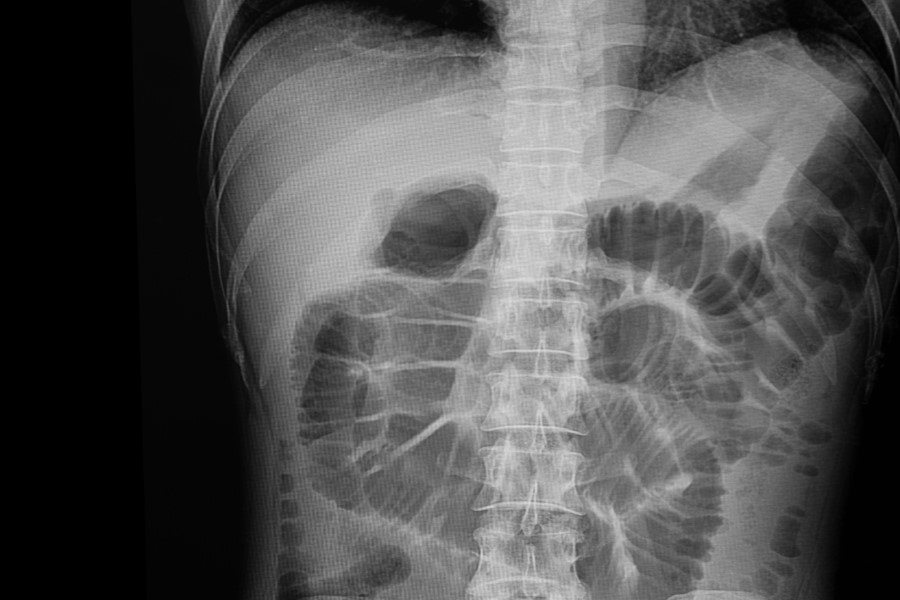

Rentgen (RTG) jamy brzusznej – przygotowanie, przebieg, kiedy wykonać?

RTG jamy brzusznej, nazywany też zdjęciem przeglądowym, umożliwia szybkie zobrazowanie narządów brzusznych, dzięki czemu pozwala na zdiagnozowanie różnych schorzeń lub uszkodzeń. Jest to dość powszechne badanie. Aby je wykonać należy posiadać skierowanie lekarskiego i odpowiednio się do niego przygotować.

RTG jamy brzusznej najczęściej jest wykonywany u pacjentów, którzy trafiają na Szpitalny Oddział Ratunkowy lub Izbę Przyjęć z ostrymi objawami perforacji lub niedrożności przewodu pokarmowego. RTG wykonywane jest wtedy w trybie pilnym, bez uprzedniego przygotowania.

RTG jamy brzusznej – jak przebiega badanie?

Po wejściu do pracowni rentgenowskiej pacjent zostaje poproszony o zdjęcie odzieży oraz wszelkich elementów metalowych z okolicy brzucha, czyli paska, kolczyków czy biustonosza z metalowymi fiszbinami. Na szyję może zostać założony fartuch pochłaniający promieniowanie w celu ochrony tarczycy, podobnie mogą zostać osłonięte okolice narządów rozrodczych, jeśli na zdjęciu ma być widoczna tylko górna część jamy brzusznej. Następnie należy ustawić się w odpowiedniej pozycji i na kilka sekund wstrzymać oddech. Prowadzący badanie przebywa w tym czasie w osobnym pomieszczeniu i komunikuje się z badanym. Cała procedura trwa zazwyczaj kilka minut, jest zupełnie nieinwazyjna i bezbolesna.